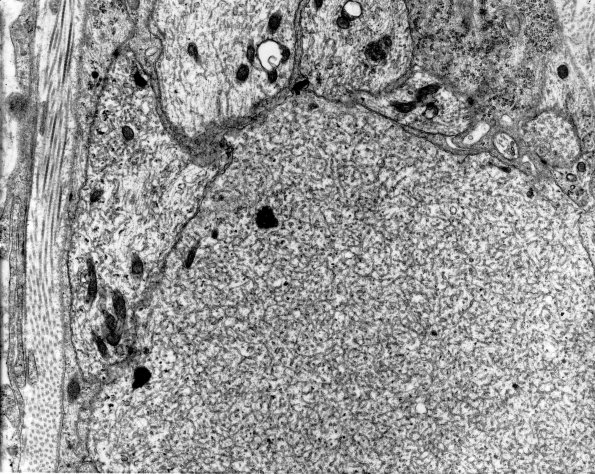

2A7 (IV-55) EM 63

Delicate tubulovesicular material is characteristic of enlarged growth cones. (electron micrograph)